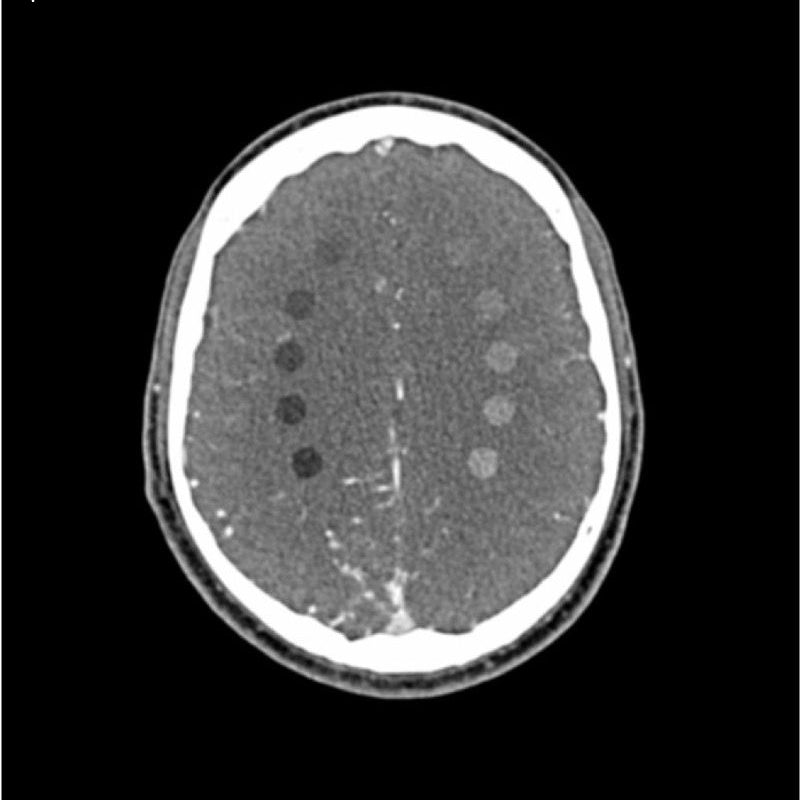

This phantom simulates a contrast medium enhanced head in arterial phase (CT angiography). It covers the vertex to the fifth cervical vertebra. The phantom has 10 low-contrast lesions in the centrum semiovale and the right hemisphere has an arteriovenous malformation.

Lesion diameter: 10 mm

Lesion height: 10.5 mm

Lesion contrast: Approx. -60 to -20 and 20 to 60 HU at 120 kVp